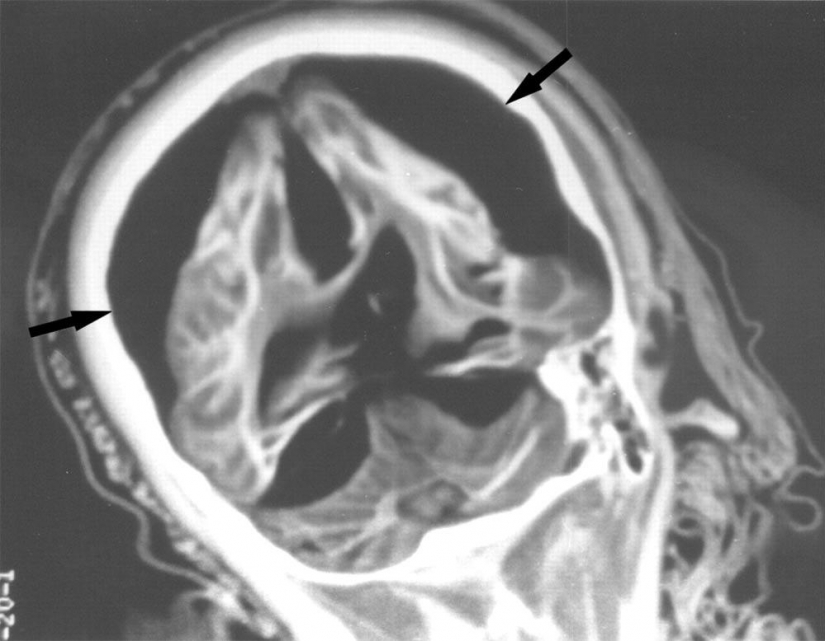

6. X-ray de el cerebro de un 15-year-old girl muestra que entre la blanca y la materia gris del cerebro hay una división. Las flechas señalan el aire que rodea el cerebro.